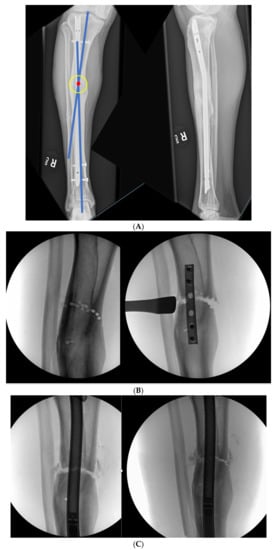

3.1. Case 1-Multifocal Correction with Intramedullary Nail: Femur

The patient is a middle-aged female with no comorbidities other than obesity who presented 26 years after an open diaphyseal femur fracture with more than 10 surgeries for attempted union and eradication of infection. The patient presented with complaints of pain at the mid-femur and knee, a chronically draining sinus of the lateral thigh, and concern for a 2-cm-short left leg. No rotational deformity is found. The limb clinically appears normal in the coronal plane. The patient has a 15-degree knee contracture. X-rays reveal a malunion of the left femur with bone sequestrum and retained hardware (Figure 6A). A metabolic workup, including the vitamin D level, is normal. The CT scan characterizes the pathological bone, allowing for precise localization of the sequestrum (Figure 6B). A deformity analysis reveals a primarily sagittal plane deformity with limb shortening. The traditional CORA analysis demonstrates translation with angulation, as demonstrated by a CORA located outside of the deformity. With the expected multiple stages, a double-level focal dome was chosen over clamshell, allowing stable weight-bearing while not requiring an extended femoral osteotomy to heal through pathological bone. The other consideration for this patient was radical en bloc resection of the diseased bone, with either bone transport or secondary reconstruction with a compressed allograft intercalary segment. This concept was reserved as the option if the current plan failed.

Figure 6.

(A) Middle-aged female with 26 years of an infected draining sinus of the left femur with malunion and shortening. The intersection of the two blue lines represents the CORA of the proximal and distal diaphyseal segments (C1). A CORA outside of the deformity reveals translation in addition to angulation. The intersection of the green line with each blue line represents an alternative where the central deformed segment is also incorporated into the analysis, revealing two CORA center points for double-level osteotomy (Ca and Cb). (B) The patient was found to have retained hardware and a bone sequestrum. Sequestrectomy with antibiotic local delivery via a coated intramedullary nail with concomitant systemic antibiotics would promote infection eradication. (C) The patient underwent double-level focal dome osteotomy at the time of initial debridement. The patient had two sequential debridements over 10 days. Stabilization using an interlocking antibiotic coated nail was placed during the final debridement. (D) Five months postoperative, where the distal osteotomy was autogenous-grafted from the patient’s contralateral femur due to the persistent osteotomy gap. Chronic suppression oral antibiotics were recommended; patient voluntarily stopped antibiotics at 24 months. (E) Three-year final follow-up with normal serological markers and no sign of recurrence. Osteotomies healed. Soft tissue healed.

The patient underwent double osteotomy using focal dome osteotomy at Ca and Cb (Figure 6C), with retained hardware removal and resection of the infected sequestrum and surrounding diseased bone. A direct lateral approach to the thigh was used, and the diseased soft tissue track was excised and analyzed by pathology. A temporary nail was inserted and replaced with an antibiotic-coated interlocking nail ten days later with a planned second debridement. The nail was compressed using the internal compression instrumentation associated with the nail. A gap in the distal osteotomy persisted despite attempted removal of the nail and re-reaming with enlarging flexible reamers. This gap was accepted with intent to revisit if bone healing did not progress. The surgical soft tissue approach healed without incident. At five months postoperative, with nonunion of the distal osteotomy at the gap, the patient underwent autograft using contralateral femur reamer–irrigator–aspirator harvesting (Figure 6D). Cultures at the grafting procedure were negative.

The patient progressed to pain-free union at both osteotomies with no recurrence of her infection over three years after osteotomy (Figure 6E).